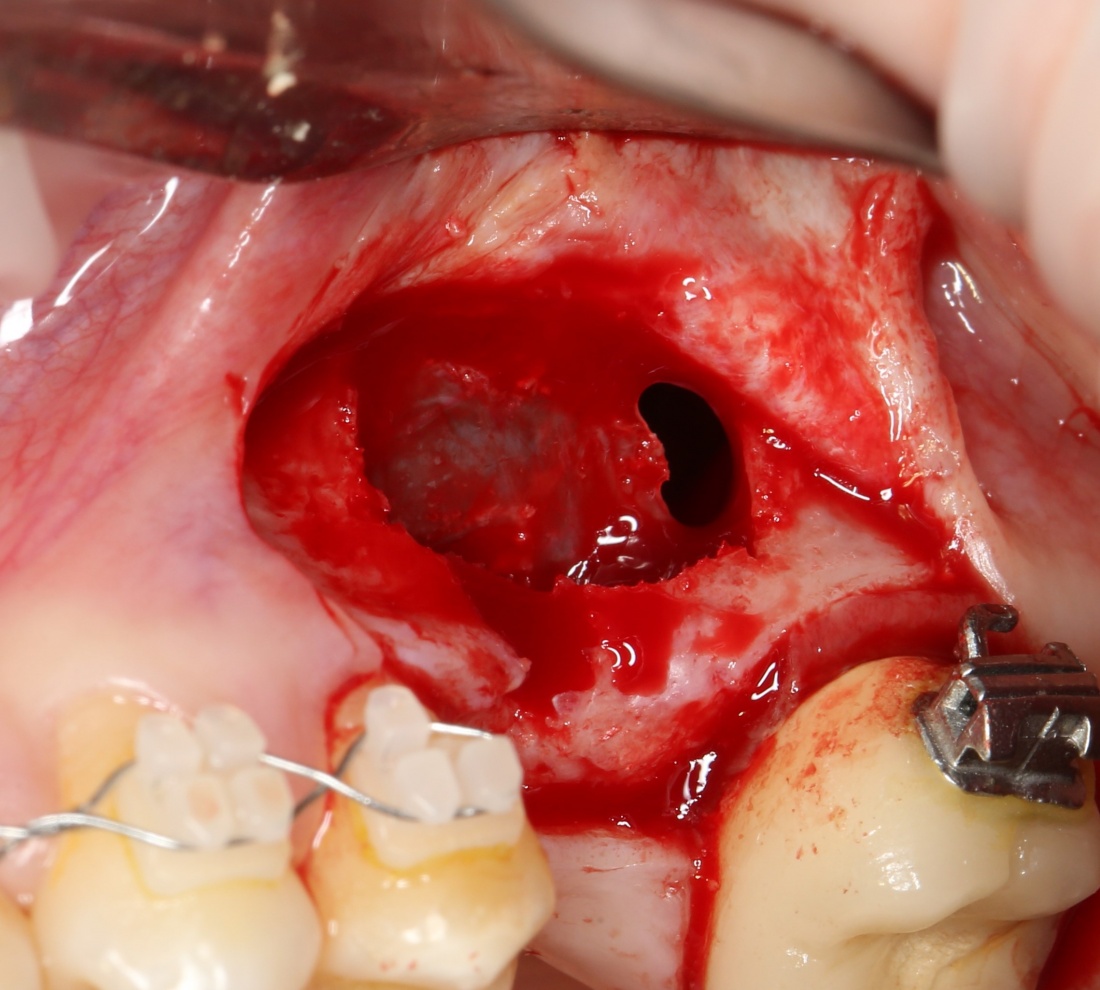

Если операция синуслифтинга проводится над только что удаленными зубами — можно смело проходить через лунки. Разумеется, после удаления зубов:

Подобный подход к формированию доступа в субантральную полость позволяет добиться обзора самых проблемных участков альвеолярной бухты, в которых вероятность повреждения шнайдеровой мембраны наиболее высока.